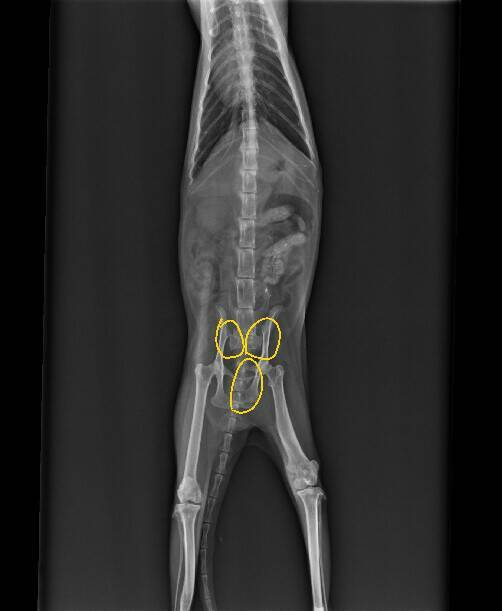

當下的小黑幾乎沒有抵抗的力氣,應該是多天沒吃飯造成的,趕緊送醫後,發現有嚴重貧血•腎衰•以及嚴重的骨盆骨折.......

聽到檢查結果,愛媽快要嚇傻了。因為血檢結果貧血很嚴重,先處理這部分,等身體狀況好些後再處理接下來的問題。動物近況說明: 經過了半個月的治療,小黑狀況有較穩定,但沒很大的起色。